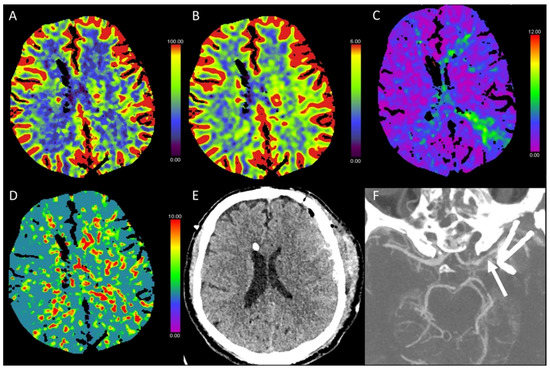

3.1. Acute Supratentorial Stroke

3.5. Hypotensive Cerebral Infarction (HCI) with Watershed Infarcts/Border Zones

3.6. Vasospasm